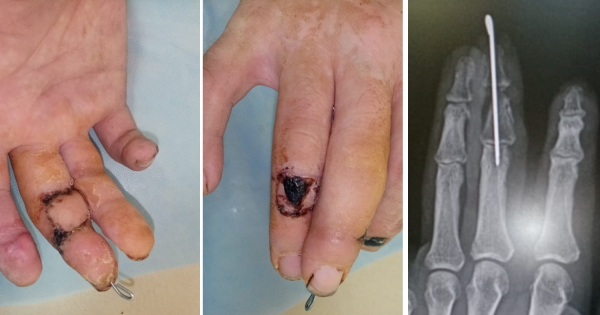

Вот рентген и рана в процессе заживления.

И когда рана III пальца очистилась, пациенту была выполнена пластика кожным лоскутом на ножке со средней фаланги IV пальца правой кисти и свободная кожная пластика с предплечья на тыльную поверхность IV пальца. Для стабилизации III пальца была выполнена трансартикулярная фиксация межфаланговых суставов через ногтевую фалангу. Хоть я и не люблю делать такой «шашлычок» на спицах, другого выбора у меня не было.